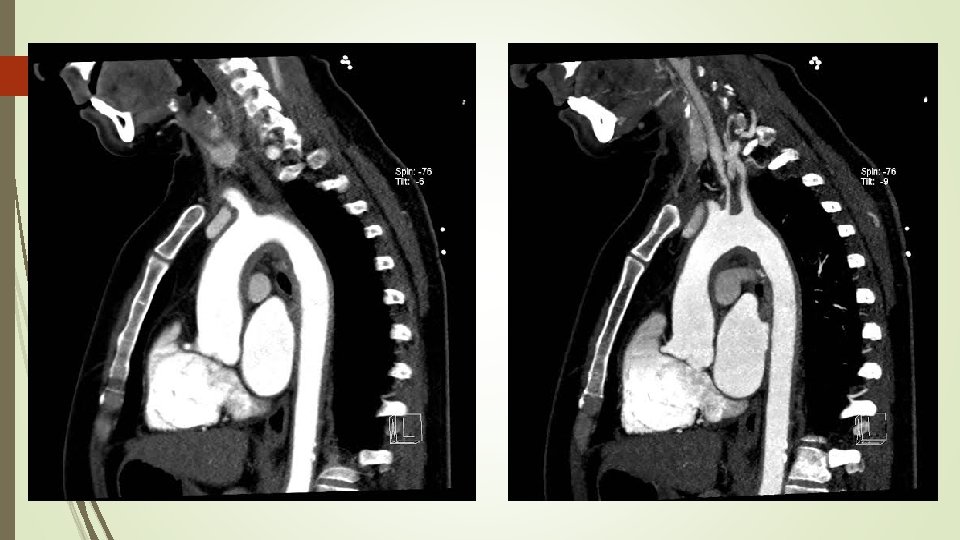

El estudio se informa como Hematoma aórtico agudo intramural tipo A, extendiéndose desde la raíz de aorta hasta la bifurcación de las iliacas primitivas. Ante dicho hallazgos, la paciente es trasladada a la Unidad Coronaria para monitorización y Cirugía Cardiaca. A las 24 horas de ingreso y previa intervención quirúrgica se solicita, angio. TAC de aorta helicoidal sincronizado para una mejor caracterización de la afectación aórtica, con los resultados que se muestran a continuación.

Angio. TAC aorta helicoidal sincronizado - Engrosamiento en forma de semiluna de aorta torácica ascendente y un engrosamiento circunferencial difuso de arco aórtico y aorta torácica descendente, alcanzando la bifurcación ilíaca. - Engrosamiento circunferencial del origen los troncos supraaórticos con estenosis filiforme del origen y primeros centímetros de carótida común izquierda. - Oclusión de arteria subclavia izquierda desde origen de arteria vertebral con repermeabilización de arteria axilar por colaterales. - Estenosis de la aorta abdominal en todo su recorrido siendo filiforme a nivel infrarrenal con diámetro mínimo de 5 mm. - Dilatación post estenótica ilíaca de común derecha. Hallazgos compatibles con Enfermedad Takayasu en fase crónica